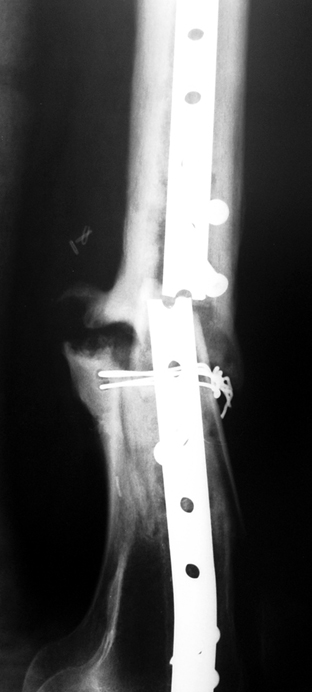

Case 3